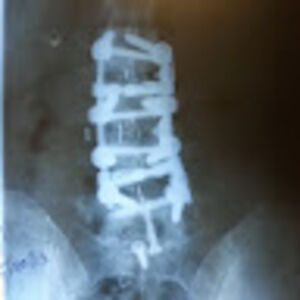

Image source: Spirited_Boat_6380